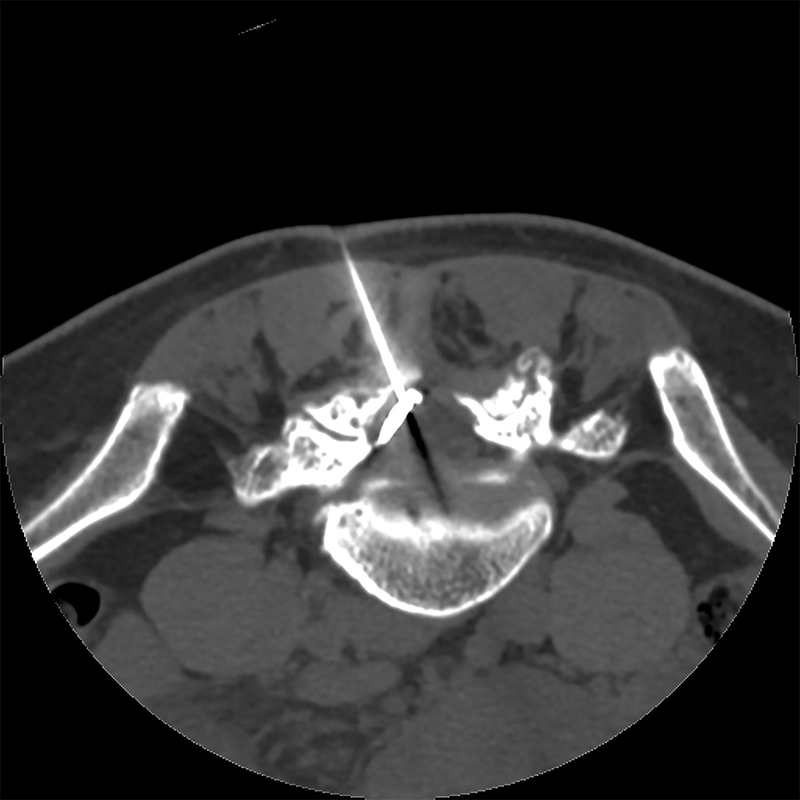

Nous réalisons les infiltrations du rachis sous contrôle scanner et sous anesthésie locale.

Ces infiltrations sont réalisées par un radiologue interventionnel sous contrôle scanner, sous contrôle échographique ou sous contrôle radiographique. Ce guidage permet d’atteindre avec une grande précision la zone à traiter.

Ensuite, un repérage de la zone anatomique sera faite par un moyen d’imagerie (scanner le plus souvent ou radiographies).

Grâce à ce repérage le radiologue interventionnel va guider son aiguille vers la zone cible tout en injectant un anesthésique local. Une fois en place dans la zone cible, il va ensuite injecté un produit de contraste iodé puis contrôler la diffusion de ce produit afin de confirmer la bonne position de l’aiguille.

Si le contrôle est satisfaisant, il réalise alors l’injection de corticoïdes. Pendant l’injection, il est possible que les douleurs de radiculalgies habituelles soient reproduites.